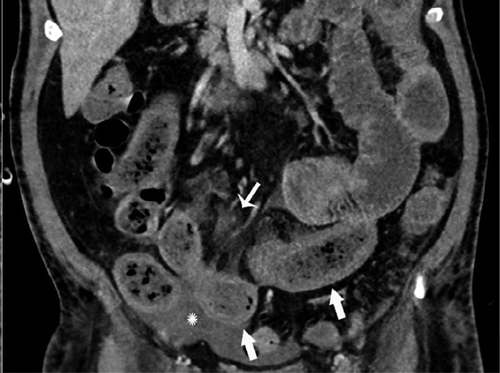

这项研究包括了412名新型冠状病毒检测阳性的患者的数据,研究人员发现,在17%的患者在治疗过程中接受腹部造影检查的患者中,近三分之一的CT扫描显示肠道异常。

“我们在COVID-19患者的影像学上发现了肠道异常,更常见的是那些去ICU的病人,”马萨诸塞州总医院的Rajesh Bhayana博士在一份声明中说。“一些研究结果是典型的缺血性肠病或肠坏死。在那些做了手术的患者中,我们看到肠坏死部位旁边的小血管凝块。ICU中的患者可能因为其他原因导致肠缺血,但我们知道COVID-19会导致凝血和小血管损伤,所以肠道可能也会受到影响。”